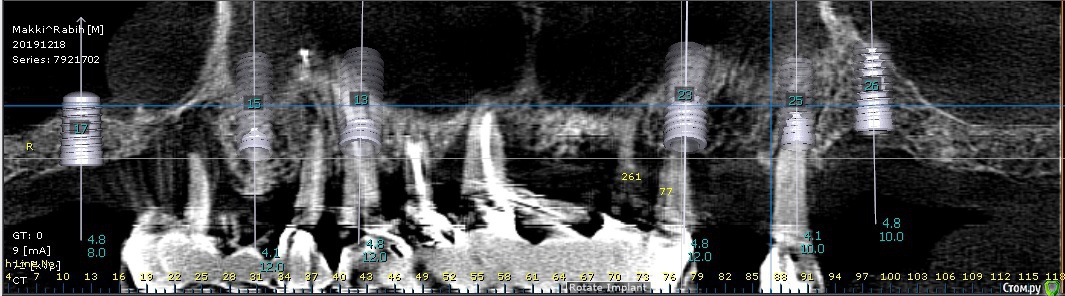

bilal Опубликовано 10 февраля, 2020 Поделиться Опубликовано 10 февраля, 2020 добрый вечер. планирую 6 имплантов на верхней челюсти. только не могу решиться ставить 1 имплант на месте 21 или 25. какие мнения? Ссылка на комментарий